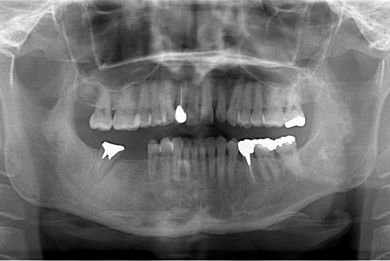

性別/年齢 女性 / 42歳

主訴 ブリッジが外れてしまった。

治療方針 セラミック治療にて審美的回復を行う。

治療内容 オールセラミッククラウン4本(オールセラミック用土台2本)

治療部位

2 1 1 2

総治療費 553,350円

治療期間 11ヶ月

治療前